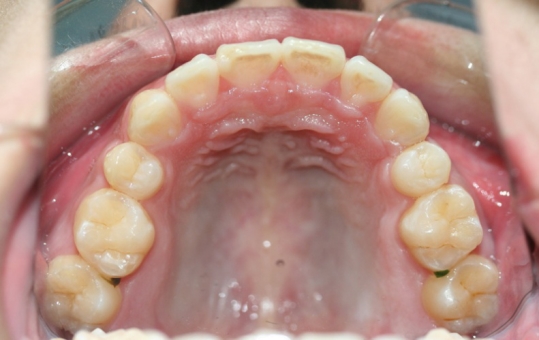

口内检查 :上下牙弓均为卵圆形 左右基本对称 上颌牙弓轻度拥挤 下颌缺失一颗下切牙

X线检查 :18、28、38、48存在,下颌缺失一颗下切牙

下颌缺失1切牙

1拔除14,24和下颌中切牙;